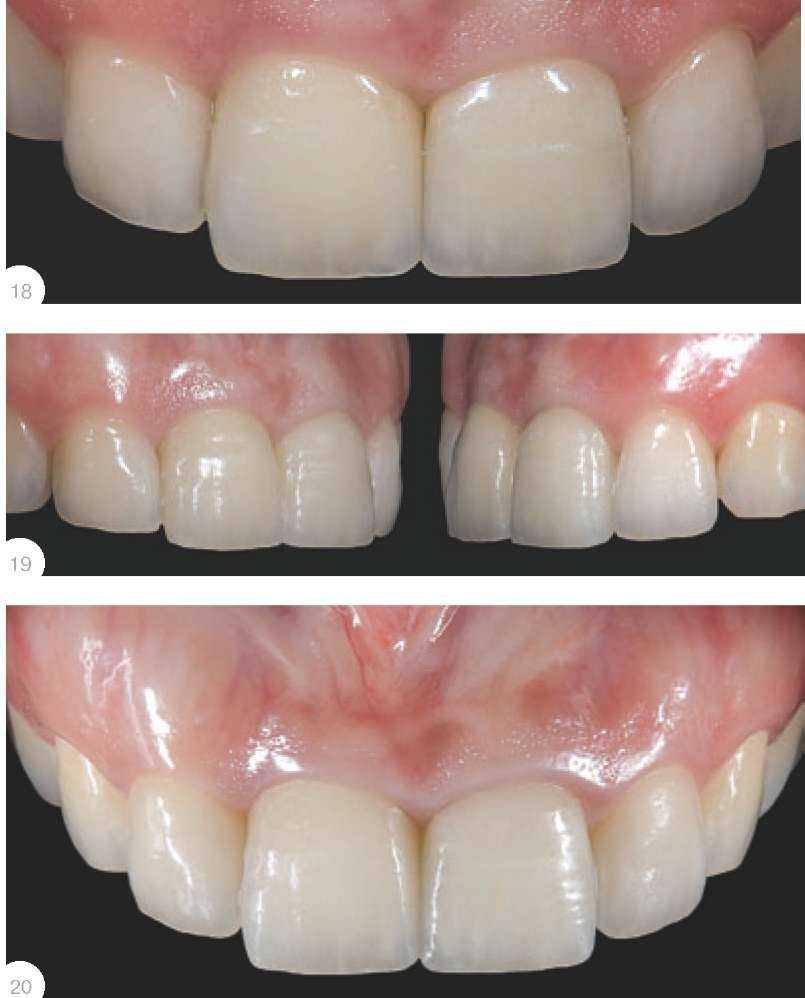

ретракционную нить без пропитки диаметром не более 000 или 00 для захвата избытка цемента.Применяя позиционер в RVG, можно увидеть факты «недопосадки»каркаса коронки на абатменте илизубах! Обратите внимание на искаженный снимок 17а, где неопытному врачу может показаться, чтоположение коронки на абатменте идеально, однако при правильном расположении позиционера виднащель в медиально-апроксимальной зоне коронки на 11 зубе. Рис. 18 - зафиксированные на самопротравливающий и самоадгезивный цемент коронки через 7дней. Ситуация через три месяцаприведена на рис. 19. По прошествии года ситуация выглядит таким образом - рис. 20. Ни у стоматолога, ни у техника, ни у пациента нетнареканий к выполненной работе.А ведь это фронтальная зона...